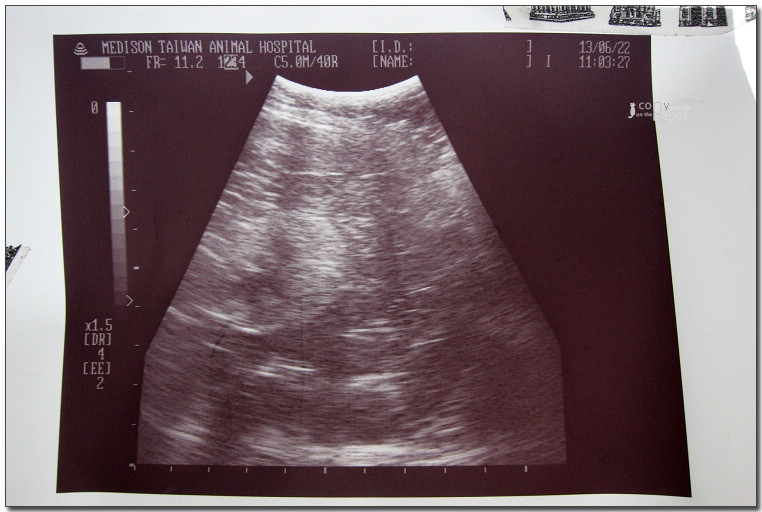

照了X光,

做了超音波,

體重6.4公斤(明明瘦瘦的,怎麼那麼重?),

好像沒什麼大礙,

打了2針,

又拿了二星期的藥,

買了化毛膏。